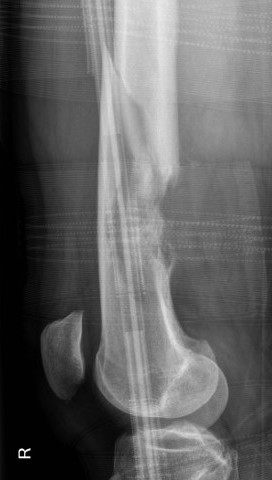

Osteosarcoma of the distal femur

Osteosarcomas of the proximal tibia

Xray

Typically metaphysis of long bones

- distal femur 35%

- proximal tibia 20%

Features

- new bone formation / osteoid

- permeative cortical destruction

- wide zone of transition

- periosteal reaction

- soft tissue mass